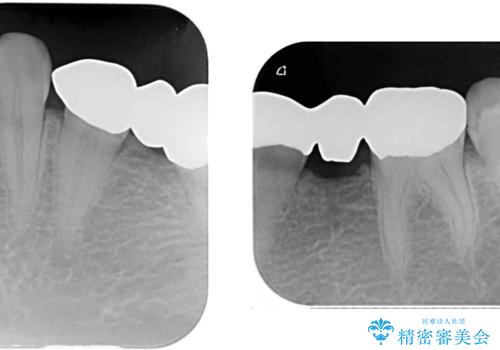

抜歯してからインプラント埋入までには時間がかかるため、その間に下顎左右臼歯の金属のブリッジをオールセラミックへ変えていくこととしました。

継ぎ接ぎだらけの上顎前歯もオールセラミッククラウンにて審美的に改善したいとのことでしたが、捻れが強くあるため、事前に矯正治療で歯列を整えてから、補綴治療を行うこととしました。